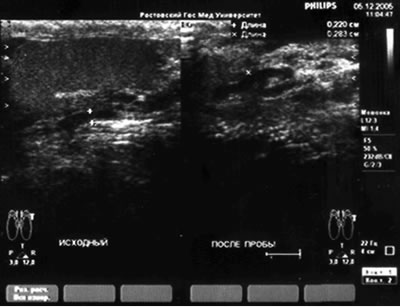

Дуплексное сканирование глубоких вен кавальной системы – диаметр вен до 2,2 мм, после пробы Вальсальвы – 2,8 мм, ретроградный кровоток – 3,2 сек